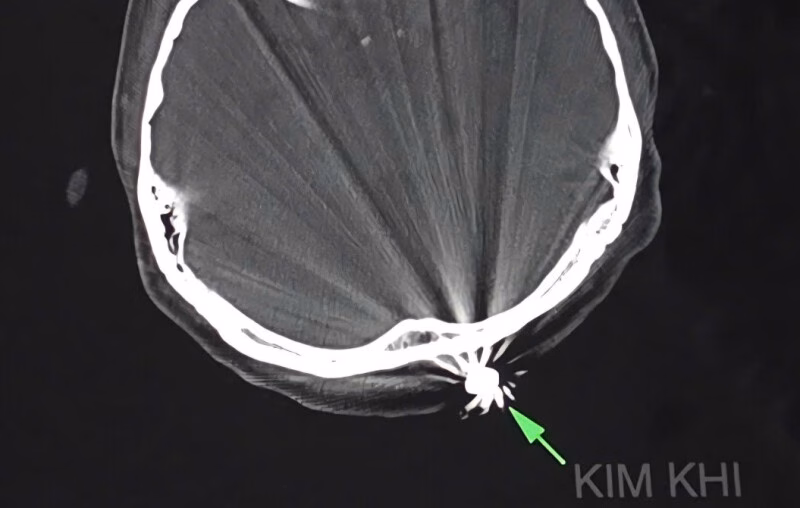

Sau khoảng 45 phút thực hiện ca phẫu thuật, các bác sĩ đã thành công lấy ra dị vật kim khí là đầu đạn có kích thước 0,5×0,3cm. Điều令人 chú ý trong trường hợp này là viên đạn chỉ xuyên qua lớp da, chạm nhẹ vào xương chẩm mà không gây tổn thương đến não và các cấu trúc lân cận. Hiện tại, bệnh nhân tỉnh táo, tiếp xúc tốt, vết mổ khô và không ghi nhận bất kỳ triệu chứng thần kinh khu trú nào.

BSCK2 Chương Chấn Phước, Trưởng khoa ngoại thần kinh BVĐKTƯ Cần Thơ, cho biết rằng vết thương do hỏa khí thường rất phức tạp và có thể gây tổn thương kết hợp nhiều cơ quan. Chúng dễ nhiễm khuẩn và khó đánh giá chính xác mức độ tổn thương qua bề mặt. Tuy nhiên, trong trường hợp của bệnh nhân T., viên đạn đã gần hết quỹ đạo bay nên lực xuyên giảm đáng kể. Nhờ đó, vết thương chỉ giới hạn ở phần mềm nông và không gây nguy hiểm đến tính mạng.